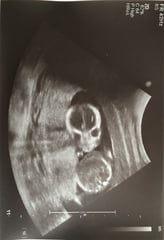

Had my 16 week scan today and found out we’re having a girl! Feels so much more real and exciting now! Baby was moving tons, it’s so freaky seeing her move so much and not being able to feel it yet. Attached photo of our little creepy alien and the gender reveal shot.